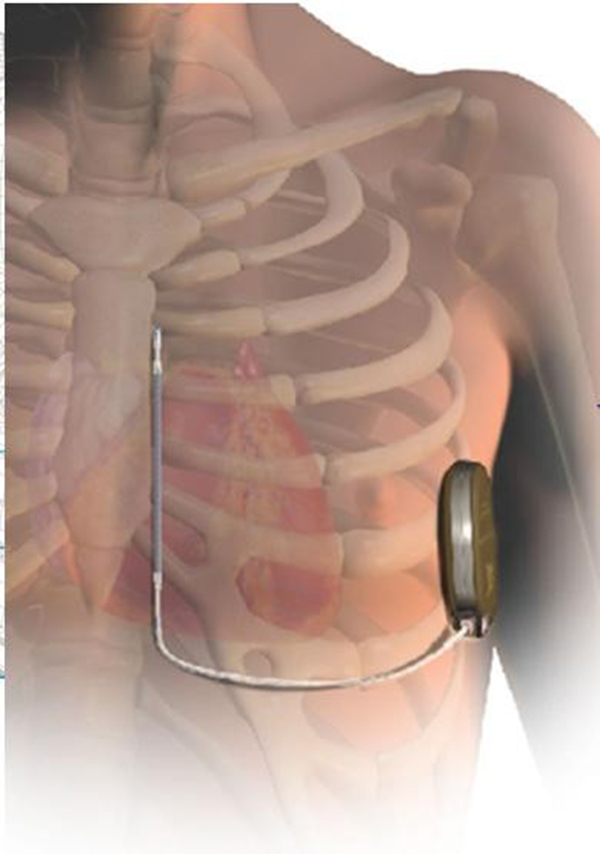

SICD主要由脈沖發(fā)生器、電極導(dǎo)線組成,與頸靜脈植入型心律轉(zhuǎn)復(fù)除顫器(TV-ICD)。不同的是,SICD的脈沖發(fā)生器經(jīng)皮下置于左側(cè)胸壁,電極是由兩個(gè)感知電極及一個(gè)電擊線圈組成,經(jīng)皮下置于胸骨旁。作為全皮下心臟除顫系統(tǒng),SICD可在一定程度上避免與靜脈導(dǎo)線相關(guān)的圍手術(shù)期及其長期并發(fā)癥,且手術(shù)過程不需要在透視下進(jìn)行。SICD的適應(yīng)人群主要包括:伴有靜脈畸形或梗阻不適合經(jīng)靜脈行心臟轉(zhuǎn)復(fù)除顫器的兒童、感染風(fēng)險(xiǎn)大及有猝死風(fēng)險(xiǎn)的年輕心律失常患者(如Brugada綜合征、長QT綜合征等)。